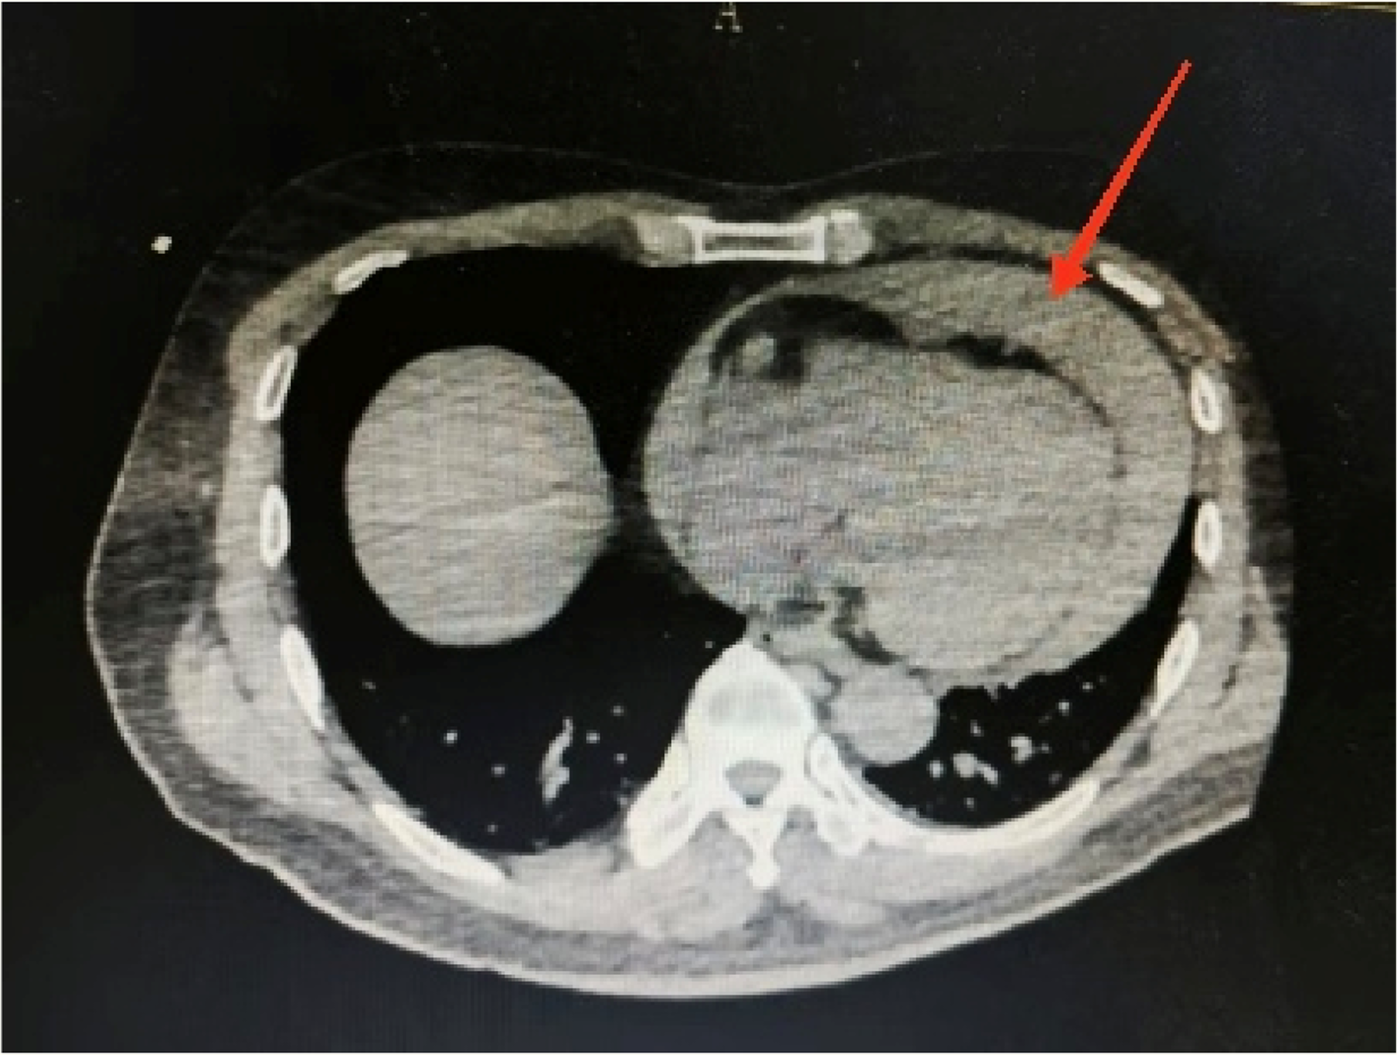

Figure 3

Aortic computed tomography angiography showing a massive hemorrhage of the pericardium.

Considering the patient’s impaired consciousness and uncooperative state, endotracheal intubation and mechanical ventilation were initiated. The initial presentation of cyanosis and cold extremities suggested circulatory shock. Bedside echocardiography, along with laboratory tests, (Table 1) indicated dilation of the ascending aorta and a substantial hypoechoic pericardial effusion (Figure 1), findings highly suggestive of aortic dissection. Once stabilized on a portable ventilator, the patient underwent emergent non-contrast cranial computed tomography (CT) and whole-aortic computed tomography angiography (CTA). Imaging demonstrated hypodense shadows along the aortic arch and anterior abdominal aortic wall, confirming an aortic arch dissection with localized rupture (Figure 2). This resulted in an intramural hematoma extending into the ascending aorta, the aortic arch, and the origin of the left common carotid artery, accompanied by massive pericardial hemorrhage (Figure 3). Cranial CT revealed no abnormalities.